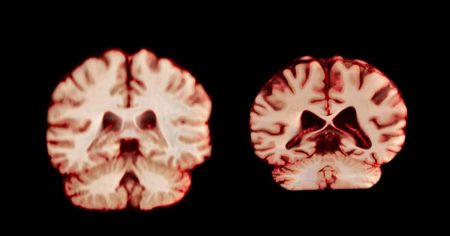

Είναι ένα από τα πιο αινιγματικά και σκληρά παράδοξα της σύγχρονης νευρολογίας. Οι γυναίκες διαγιγνώσκονται με Alzheimer σχεδόν δύο φορές…